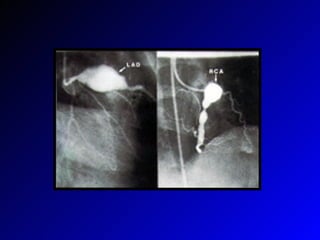

KH-anevrizma Koroner arter anevr. %25-40 %50, 5 yıl içinde geriler 3-4 mm---2 yıl içinde geriler  >8 mm---Kötü prognoz(stenoza bağlı koroner tromboz, MI, ölüm) Erken koroner arter atheroskleroz gelişimi

İzlem-II Anevrizma>8 mm ise---stress testi, koroner anjiografi( stenoz?), + warfarin Zorlu egzersizden kısıtlanmalı Koroner arter stenozu varsa---revaskülarizasyon Periferal arter anevrizmaları---periferal iskemi, gangren---trombolitik tedavi, antikoagulan

KH-anevrizma Koroner arteranevr. %25-40 %50, 5 yıl içinde geriler 3-4 mm---2 yıl içinde geriler >8 mm---Kötü prognoz(stenoza bağlı koroner tromboz, MI, ölüm) Erken koroner arter atheroskleroz gelişimi